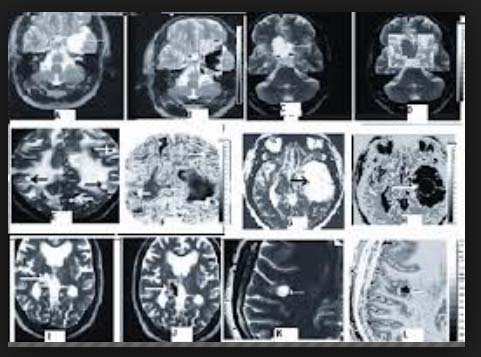

Sau khi thăm khám và điều tra bệnh sử, chụp cắt lớp vi tính có hoặc không có bơm thuốc cản quang đường tĩnh mạch là bước đầu tiên trong chẩn đoán các ca bệnh nghi ngờ ATSL thần kinh. CT não có hoặc không có thuốc cản quan sẽ cho thấy hình ảnh các tổn thương điển hình của ATSL đường kính nhỏ hơn 20mm và không có hình ảnh phản đứng giữa là hình ảnh gợi ý cao cho thể ATTSL thần kinh. Phần scolex, hoặc phần giác hút của ấu trùng cũng có thể nhìn thấy; đây là đặc trưng bệnh của ATSL thể thần kinh.

Số lượng, kích thước và vị trí có nang xuất hiện cũng như giai đoạn chu kỳ của nang sán, có thể xác định và có thể tác động đến việc quyết định điều trị. Các nang là các hình ảnh tổng thương dạng điểm có thể phát triển và tồn tại được, nang không bị thoái hóa. Các tổn thương dạng nang chỉ ra biến tính hoặc thoái hóa có một vài phản ứng viêm bao quanh. Cuối cùng, các nang hình thành calci hóa là một bằng chứng các nang đã tồn tại lâu có thể đã chết. Chăm sóc phải được tiến hành khi có thể còn nghĩ đến nhiều nguyên nhân khác (lao, bệnh ký sinh trùng khác, di căn từ nơi khác đến, hoặc ung thư nguyên phát của não hoặc hình ảnh abces não) khi một tổn thương tìm thấy trên phim chụp cắt lớp.

Hình ảnh trên phim chụp cộng hưởng từ cũng là công cụ hữu ích để chẩn đoán ATSL thể thần kinh và có thể tốt hơn cả chụp cắt lớp CT để phát hiện các thương tổn trong não tủy, trong cuống não, trong não thất. Việc áp dụng nó nên cân nhắc khi CT-scanner không chẩn đoán ra. CT và siêu âm là rất nhạy để phát hiện các tổn thương ATSL tại mắt và hệ cơ xương.